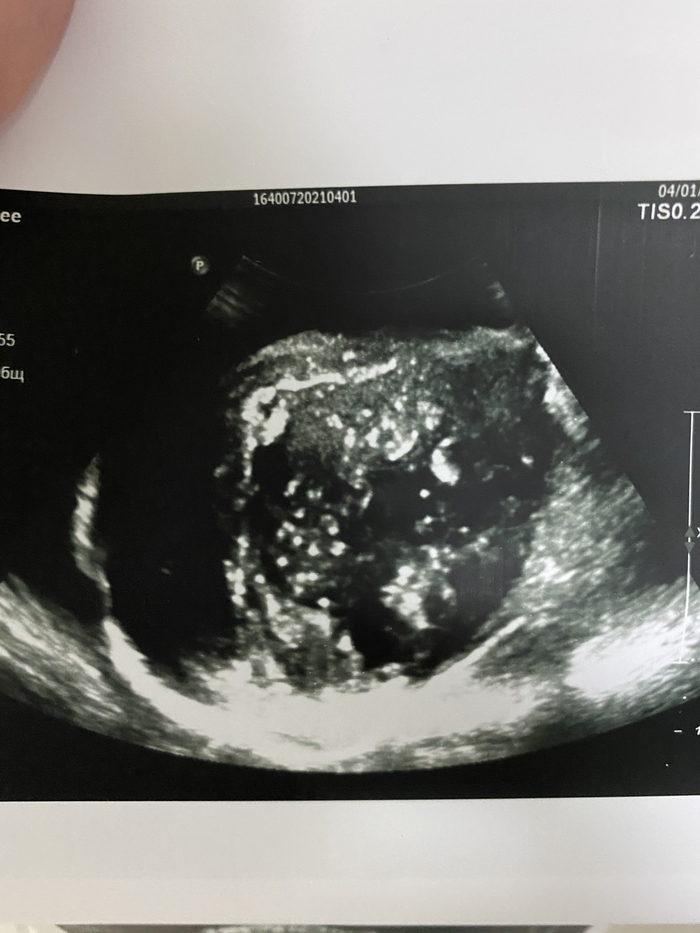

Было назначено УЗ-исследование вен нижних конечностей, которое исключило тромбоз, но при попытке вывести подвздошные сосуды, в полости малого таза оказалось случайной находкой объёмное образование, которое представляет из себя конгломерат из петель кишечника и предстательной железы.

Крайне сложно напугать врача, пусть и с не очень большим стажем в 10 лет. Но собственно, что ожидала, то и увидела. Увеличенная мошонка, несколько покрасневшая, но когда поставила датчик, то мне прям стало почти физически больно.

Не получается у меня прикрепить видео ультразвуковой картинки, как выглядят яички при раке.

Оставлю так и попробую вставить фото.

На фоне гидроцеле (скопления жидкости в мошонке) визуализируются идентичные друг другу изменённые яички и придатки, слабо дифференцируется ткань яичек, кровоток сохранен.